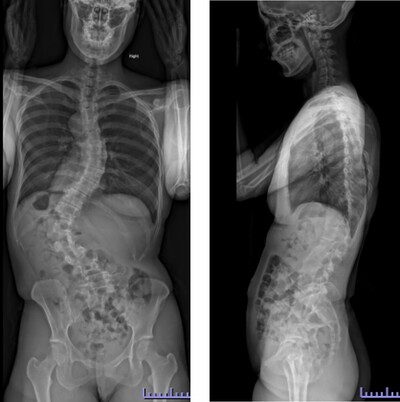

思春期特発性側弯症の全脊椎レントゲンで背骨がSの字に曲がっています。最も曲がっている箇所は52°で、成長終了後も高率にカーブが進行し続けます。50°前後の側弯であれば手術により80%以上まっすぐにすることができます。通常は70%程度の矯正率で良いとされていますが、本来出来るだけまっすぐする手術であり、バランスが損なわれるようなことがなければ我々は矯正率80%を目指しています。

この症例は術後の側弯角は8°で、矯正率は85%でした。また肩バランスも水平で保たれています。また注目すべきは腰の曲がりです。術前のレントゲンをみると腰にも側弯があるのが分かります。(黄色矢印)

腰椎の可動性を残すために、胸椎の側弯に絞って矯正固定を行い腰椎の側弯が引っ張られて改善することを期待しました。術後のレントゲンをみると金属が埋め込まれていない腰椎の側弯が大きく改善しているのが分かります。(黄色矢印)

この症例についても、横から見ると術前に右の背中が肋骨隆起(リブハンプ)により出っ張っています。(赤色矢印)

手術により側弯だけでなく回旋矯正、生理的胸椎後弯形成が成され、術後は右の背中の出っ張りがなくなり生理的な背中全体の丸みが復元されているのが分かります。(赤色矢印)

このように我々は側弯だけでなく、本来の生理的なshapeを取り戻すことを目標に治療を行っています。